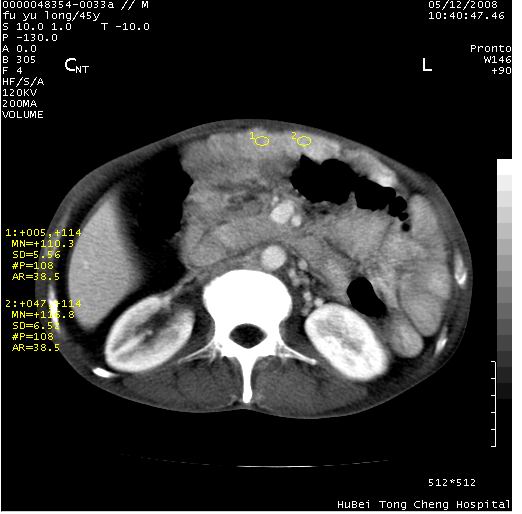

以下是引用医影拾贝在2008-5-30 2:38:00的发言:[br]气肿性胃炎、胃十二指肠溃疡、腹膜炎,考虑穿孔可能性较大

以下是引用lkc8963在2008-5-30 8:44:00的发言:[br]胃窦癌伴网膜(胃结肠韧带)/腹膜及腹膜后淋巴结转移.